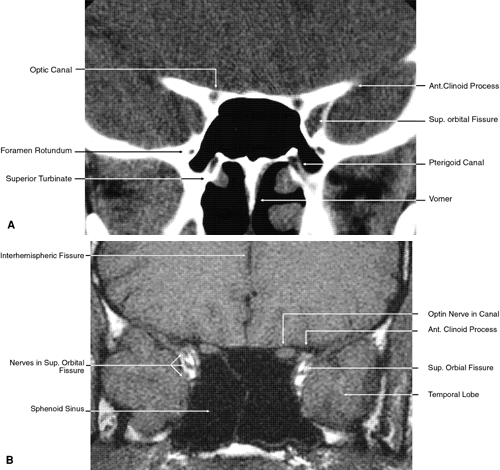

Fig. 17. Coronal images through anterior orbit. A. Computed tomography scan. B. T1-weighted magnetic resonance imaging.

Fig. 18. Coronal images through midglobe. A. Computed tomography scan. B. T1-weighted magnetic resonance imaging.

Fig. 19. Coronal images through midorbit posterior to the globe. A. Computed tomography scan.B. T1-weighted magnetic resonance imaging.

Fig. 20. Coronal images through orbital apex. A. Computed tomography scan. B. T1-weighted magnetic resonance imaging. C. Anatomic section of a cadaver head at the level of the orbital apex.

Fig. 21. Coronal images through optic canal. A. Computed tomography scan. B. T1-weighted magnetic resonance imaging.

Fig. 22. Axial images at the level of inferior orbit. A. Computed tomography scan. B. T1-weighted magnetic resonance imaging.

Fig. 23. Axial images at the level of midorbit. A. Computed tomography scan. B. T1-weighted magnetic resonance imaging.

Fig. 24. Axial images at the level of superior orbit. A. Computed tomography scan. B. T1-weighted magnetic resonance imaging.

Fig. 25. Axial images at the level of tendon of the superior oblique. A. Computed tomography scan. B. T1-weighted magnetic resonance imaging.

Fig. 26. T1-weighted magnetic resonance imaging; sagittal image through optic nerve.

The globe is shown in Figure 12. The orbit and periorbital structures are shown in Figures 13 through 16, and the optic canal is shown in Figures 17 through 26. The cavernous sinus and optic chiasm are shown in Figures 27 and 28, and the posterior visual pathway and cranial nerves are shown in Figures 29 through 33.